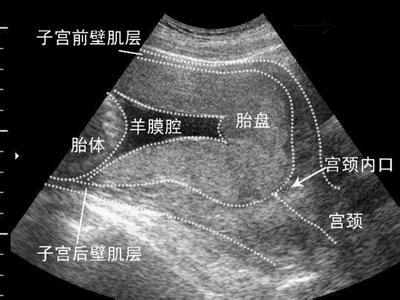

第二天进行的B超显示,小王宫内妊娠单活胎,胎儿大小相当于孕28周,中央型前置胎盘声像,胎盘漩涡形成,考虑胎盘植入声像。

到了第五天,小王做了盆腔的核磁共振,检查结果显示,子宫肌层中下部变薄且与胎盘分界不清。

“根据核磁共振的结果 ,我考虑胎盘植入可能性大,膀胱壁未见明确受侵征象,多是女中央型前置胎盘,”姜医生作出了结论:“虽然患者现在有阴道出血,但最好能保胎到36周。”